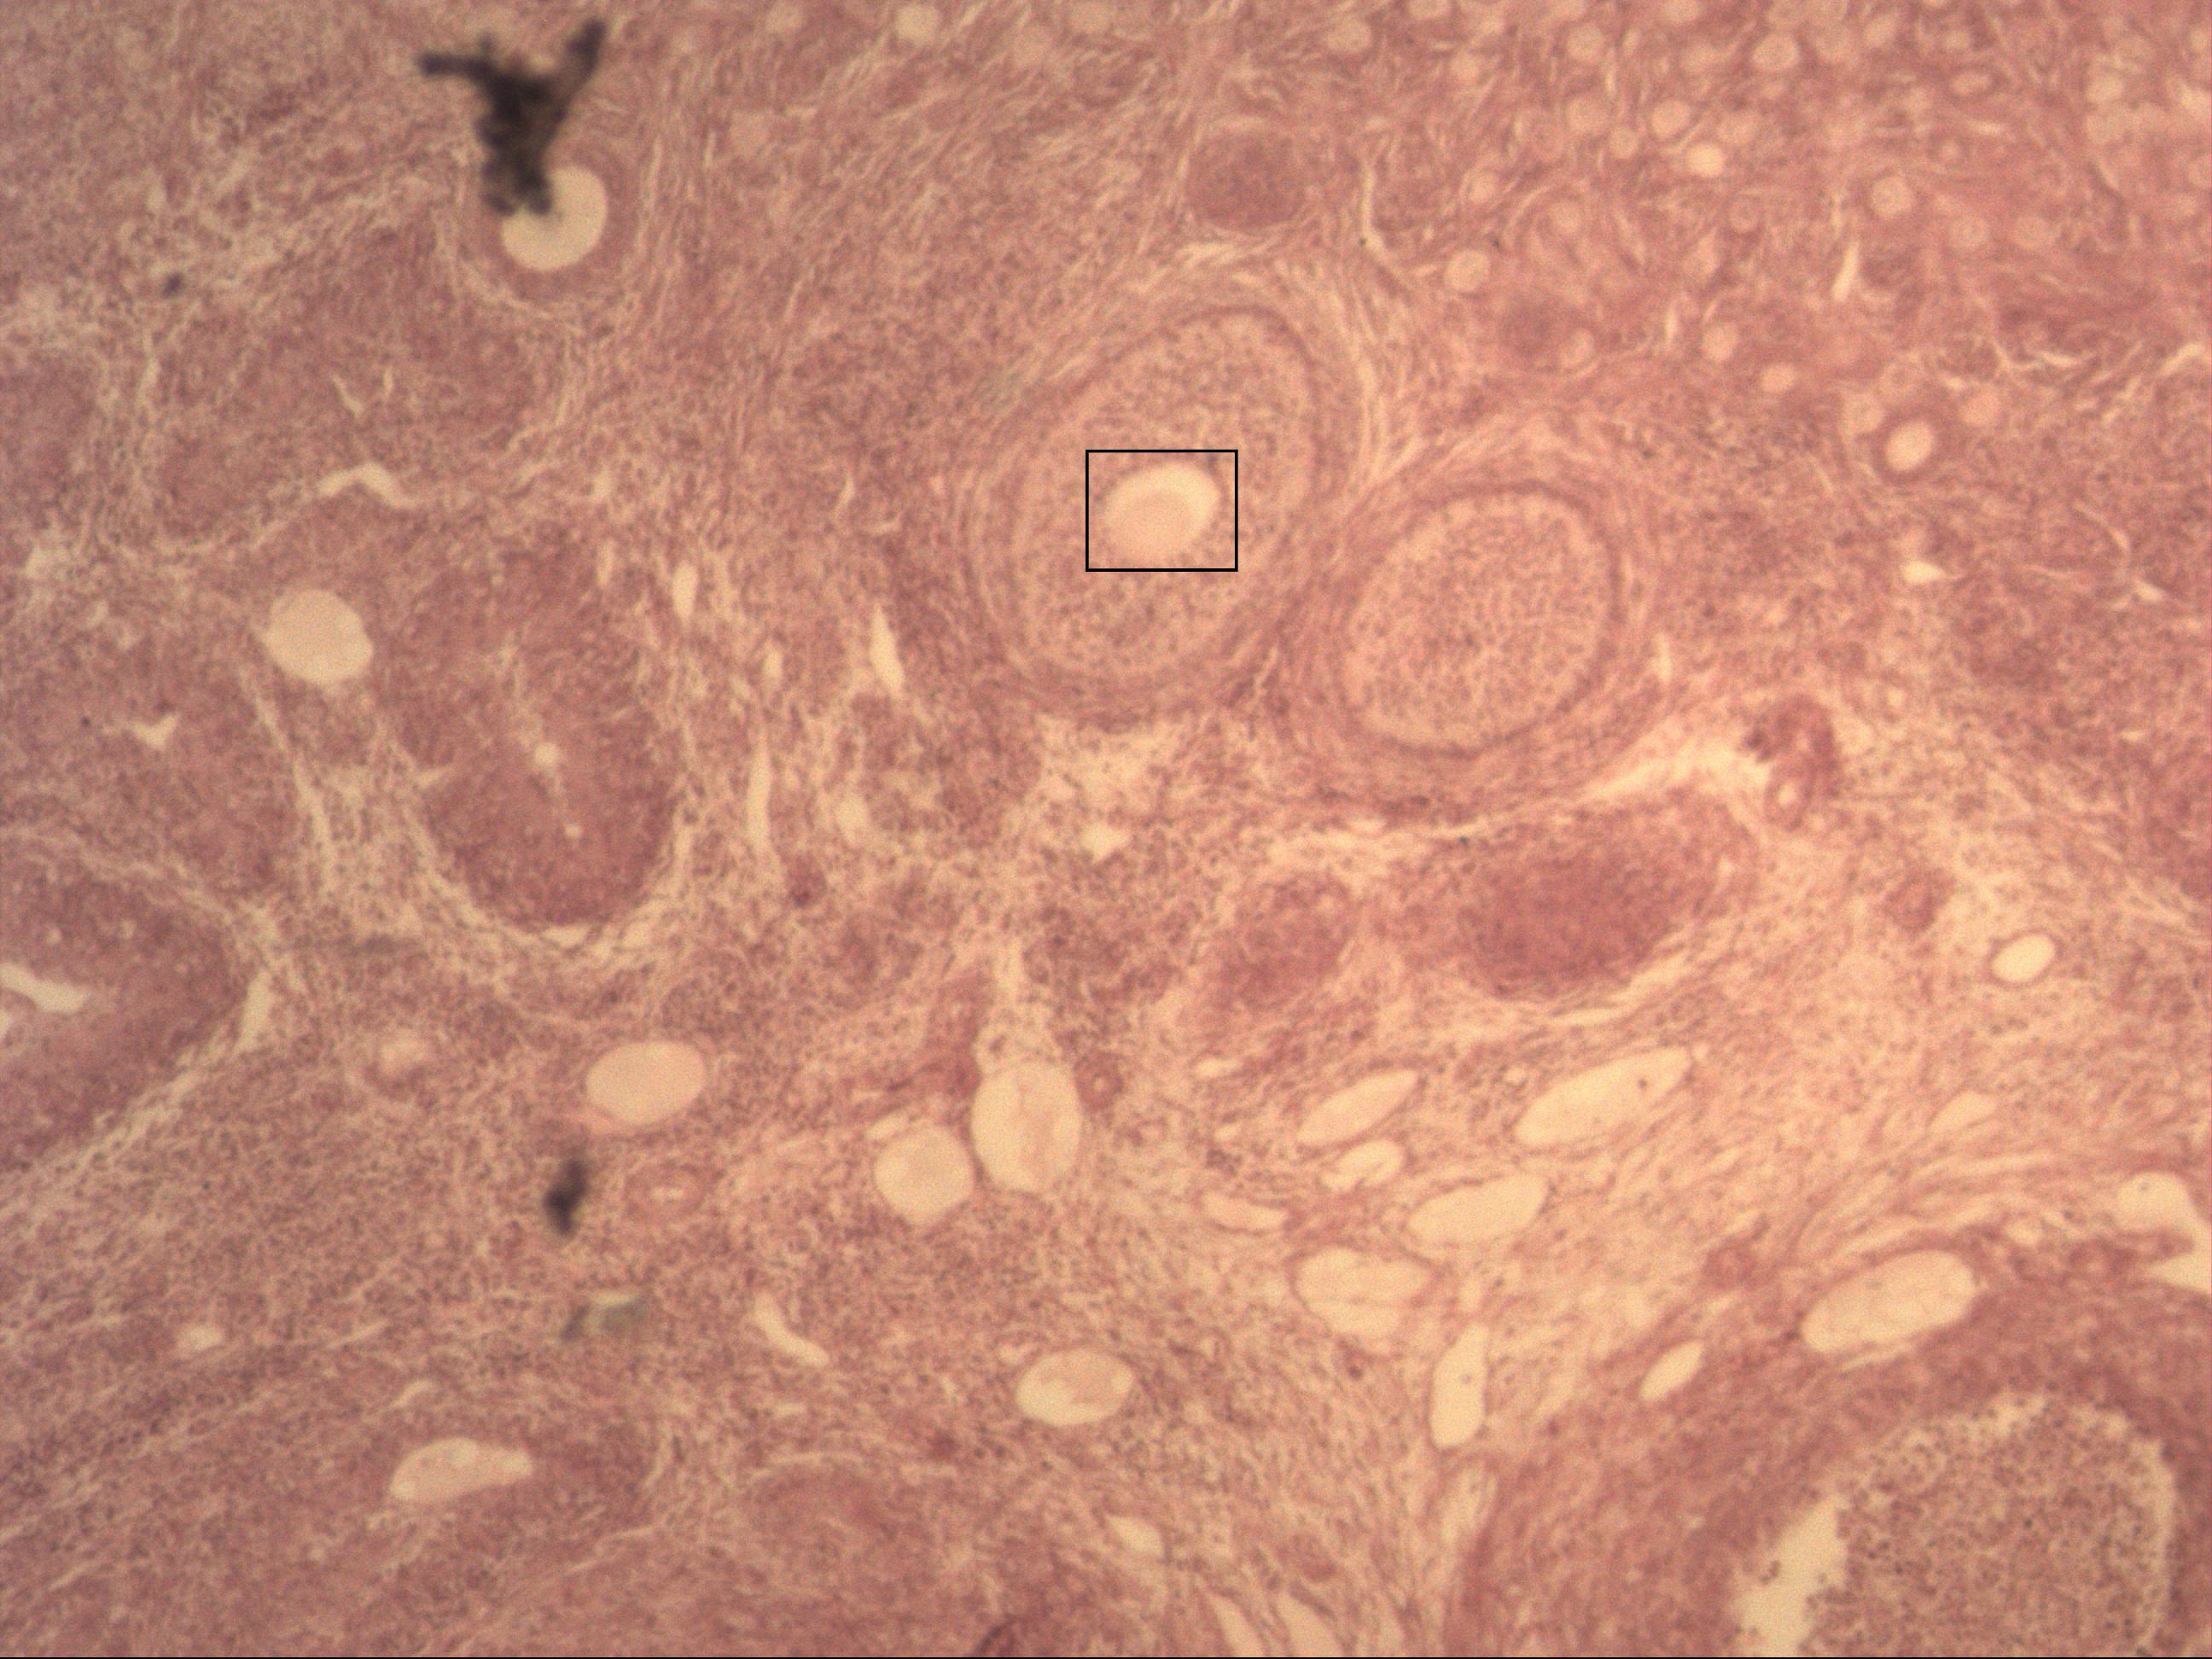

Zonula pellucida (zwischen Oozyte und Follikelepithel)

Primärfollikel

Sekundärfollikel

Oozyte

Primordialfollikel

Im Eierstock findet man die Ovarialfollikel ("Bläschen"). Die Entwicklung dieser wird in die folgenden Phase eingeteilt: Primordialfolikel (einschichtig flaches Epithel), Primärfollikel (einschichtig kubisches Epithel, Zona pellucida).